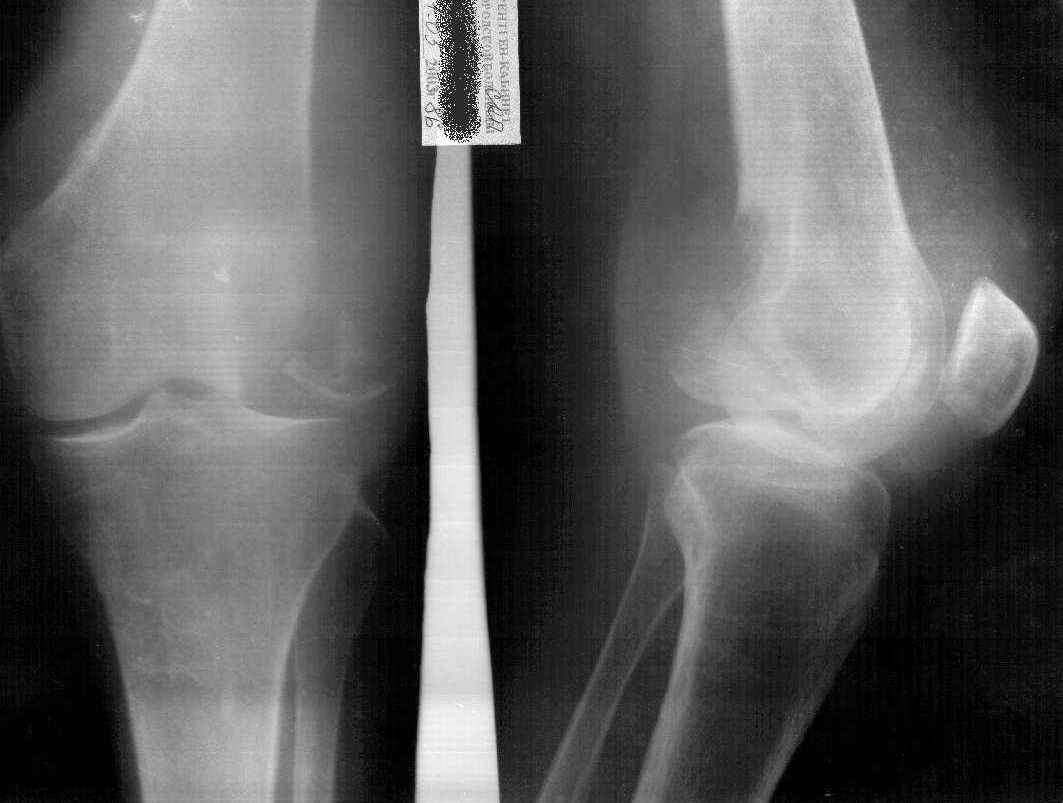

Больная К.85 лет, получила незначительную травму в конце июля 2002 года (рентгенограммы от 26.07.2002). Ушиб коленного сустава, отека не было, гемартроза не было. Лечилась местными средствами, троксевазиновая мазь, водочные компрессы. В дальнейшем развился посттравматический периартрит правого коленного сустава, синовиит правого коленного сустава. Больная на дом приглашала много различных врачей, из санаторной сети, частных хирургов, из скудных полученных данных возможно было выяснить, что получала диклофенак-натрий внутримышечно, примерно 10 раз. Несколько внутрисуставных инъекций, сколько и с каким промежутком выяснить не удалось, но более менее достоверно, что один раз вводили гидрокортизон и один раз кеналог-40. Записи практически никто не оставлял.На данный момент больная категорически отказывается от госпитализации в любое из предложенных отделений ни только для лечения, но и для обследования. Ищет врача, который назначит "правильную" мазь.Моя версия, асептический некроз наружного мыщелка правого бедра, после многократного введения гормональных противовоспалительных препаратов (рентгенограммы от 07.05.03).

Если верить клинике (отсутствие гемартроза) говорить о первичном переломе наружного мыщелка бедра нельзя. Да и не ходила бы больная с таким переломом. Плюс ко всему, практически, не бывает при данной локализации переломов без смещения.

Моё мнение: Асептический некроз наружного мыщелка бедра с патологическим переломом и рассасыванием приферического фрагмента.

Картина близкая к асептическому некрозу головки бедра при медиальном перломе шейки бедра - но в этом случае перелом первичен, а некроз вторичен.

Лечение симптоматичекое, хождение с палочкой или костылём.

Еслии верить многократному применению гормональных препаротов, то первичный (без травмы) асептичесий некроз имеет право быть. Даже не столько асептический некроз, сколько остеопоротическая резорбция костной ткани медикаментозного происхождения.